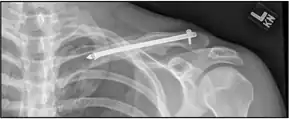

| X-ray of a left clavicle fracture | |